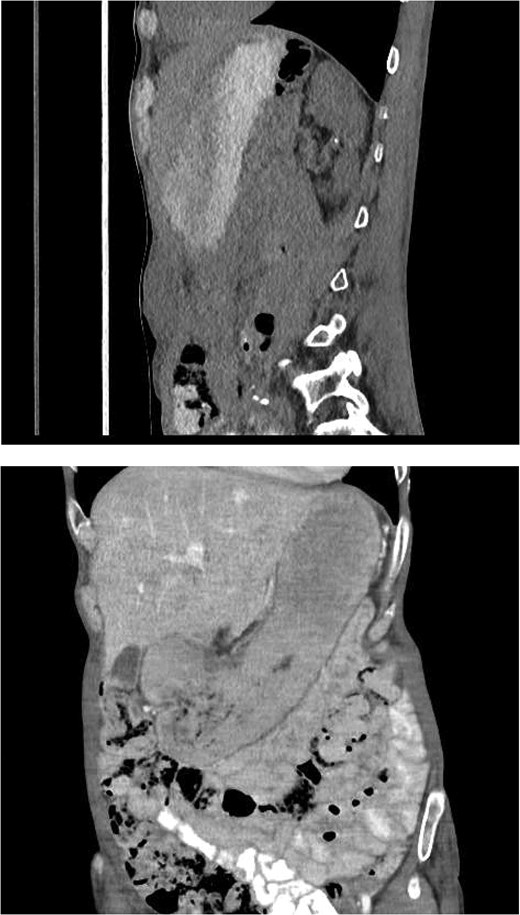

CT abdomen (Fig. 3): A multiloculated fluid collection at the superior greater omentum (7 × 3 × 4.6 cm) inseparable from the gastric antrum, extending into the anterior abdominal wall with a subcutaneous collection (9 × 3.5 × 2.8 cm). No free air or fluid.

CT abdomen showing a multiloculated fluid collection at the superior greater omentum (7 × 3 × 4.6 cm) inseparable from the gastric antrum, extending into the anterior abdominal wall with a subcutaneous collection (9 × 3.5 × 2.8 cm). No free air or fluid.